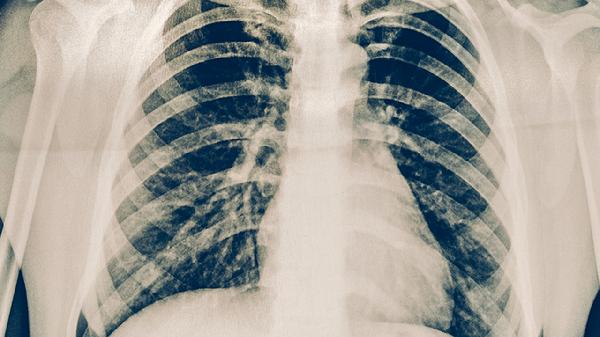

肺結(jié)核患者應(yīng)注意保持室內(nèi)空氣流通,避免與他人密切接觸以防止傳染。飲食上應(yīng)保證充足營養(yǎng),多攝入富含優(yōu)質(zhì)蛋白的食物如雞蛋、牛奶等,適當(dāng)補充維生素以增強免疫力?;颊咝鑷栏褡襻t(yī)囑完成全程抗結(jié)核治療,不可自行停藥,定期復(fù)查胸部影像學(xué)檢查。出現(xiàn)癥狀加重或藥物不良反應(yīng)時應(yīng)及時就醫(yī)。